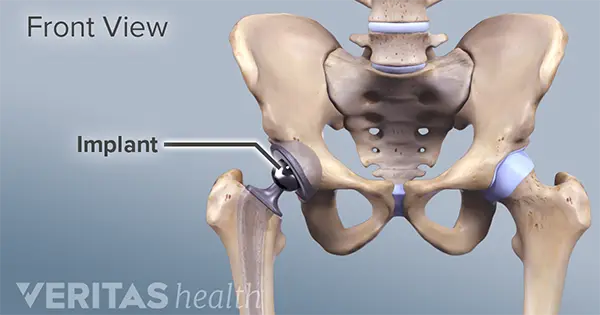

تعویض مفصل لگن

تعویض مفصل ران، از جمله جراحی هایی است که در حوزه ارتوپدی انجام می شود و درصد رضایت و موفقیت بالایی را به همراه دارد. دلیل اصلی انجام این روش جراحی…..

تعویض مفصل لگن به روش کم تهاجمی

در این روش عمل تعویض مفصل با برش هایی که اندازه کوچکتری دارند انجام می گیرد، هدف اصلی از انجام این جراحی کمتر شدن میزان خونریزی ،بهبود شرایط بیمار با حداقل آسیب وارده به عضلات بیمار ، دوره نقاهت کمتر وبهبودی سریعتر وی می باشد….